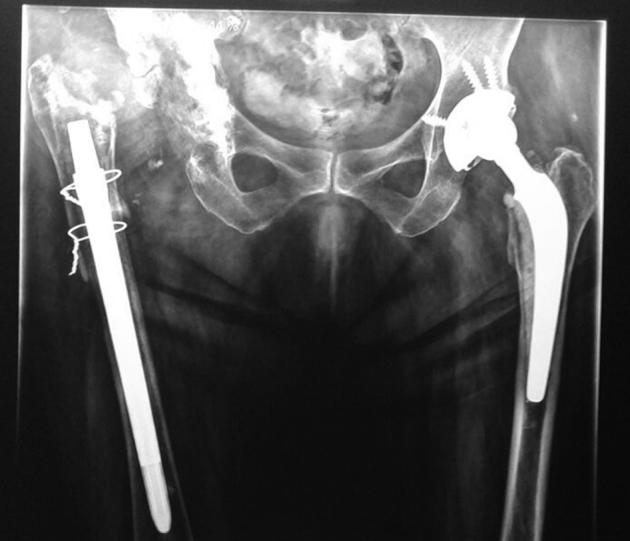

An immunocompromised patient with a history of multiple hip implant revisions extended courses of empiric antibiotic treatment, and a retained metallic rod in the femoral medullary canal was transferred for diagnostic studies and treatment. A high suspicion of fungal infection and utilization of extended and specific fungal cultures were the diagnostic keys for infection with . The treatment consisted in a debridement surgery with the use of a functional spacer with cement supplemented with voriconazole and vancomycin plus a 6-month systemic treatment with voriconazole. After 2 years of follow-up, the patient is free of symptoms.

一名有多次髋关节植入物翻修史、接受过经验性抗生素延长疗程治疗且股骨髓腔内留有金属棒的免疫功能低下患者被转诊进行诊断性检查和治疗。高度怀疑真菌感染并采用延长疗程及特定真菌培养是诊断感染的关键。治疗包括使用含伏立康唑和万古霉素的骨水泥功能性间隔物进行清创手术,以及随后6个月的伏立康唑全身治疗。经过2年的随访,患者无症状。